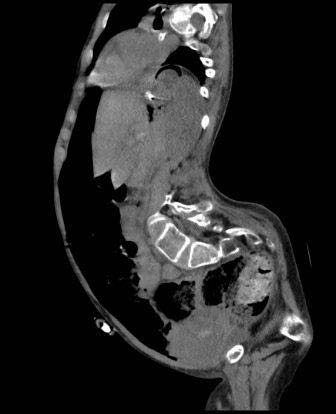

A 14 years old female known case of cerebral palsy, epilepsy, spinal deformities and fixed flexion deformities of upper and lower limbs who was in longterm nasogastric feeding was admitted electively to our hospital for insertion of percutaneous gastrostomy feeding tube. She had the procedure done under conscious sedation. Size 14 Fr feeding pigtail-retained catheter was inserted percutaneously into the stomach under fluoroscopic guidance. The patient tolerated the procedure well without immediate complications (figure 1) however, she failed to tolerate feeding through the gastrostomy tube and the tube had to be clamped. She also developed frequent vomiting and increasing abdominal distension over the forty-eight hours after the procedure. She had abdominal x-rays which revealed suspicious of free intraperitoneal air (figure 2). Shortly after the CT scan, the patient's condition deteriorated rapidly. She became confused with pulse rate over 130/minute and systolic blood pressure below 90 mm of Hg and she started to drop her oxygen saturation. Her abdomen became more distended, tympanic and rigid. She was rushed to the operation room for laparotomy. The abdomen was explored through an upper mid line incision. The patient had immediate response after entering the abdomen, her pulse rate started to come down and her blood pressure started to build up. The stomach was found not fixed to the anterior abdominal wall with about 5 cm of the tube between the stomach and the abdominal wall. The free intraperitoneal fluids were sucked out and testing for gastric leak by methylene blue injection through the nasogastric tube demonstrates leaking around the gastrotomy tube (photograph 1). The tube was secured to the stomach with double purse string sutures and the stomach was fixed to the anterior abdominal wall. The patient was kept ventilated for 24 hours and remained hemodynamically stable. Feeding through the gastrotomy tube was assumed on the second postoperative day and was well tolerated by the patient.

An erect chest x-ray is probably the most sensitive plain radiograph for the detection of free intraperitoneal air which shown the Dome sign demonstrated by the presence of bilateral dark crescent of gas under both hemidiaphragm. (35) Massive free intraperitoneal air may demonstrate cupola sign which refers to non-dependent gas that rises within the abdominal cavity of the supine patient to accumulate underneath the central tendon of the diaphragm in the midline. It is seen as lucency overlying the lower thoracic vertebral bodies with well-defined superior border and ill-defined inferior margin. (36) multiple signs of free intraperitoneal air were described on supine abdominal radiographs including the double wall sign also known as Riegler sign which it is a sign of pneumoperitoneum with gas outlining both sides of the bowel wall result from presence of extra and intra luminal gas, usually seen when large amounts of free gas, >1000 mL, present within the peritoneal cavity, the falciform ligament sign (also called the Silver sign) is a sign seen with a pneumoperitoneum resulting from outlining of the falciform ligament with free intraperitoneal gas in a supine patient and the football sign (the intraperitoneal outlines the abdominal cavity, the falciform ligament appears like the laces of a football). (37) CT scan is considered superior to simple plain radiograph in detecting the presence of pneumoperitoneum (38) and usually capable of demonstrating the presence of intra-abdominal free air in patients who had no evidence of pneumoperitoneum on chest radiograph. (25) but is usually not needed for confirmation of the diagnosis in cases of tension pneumoperitoneum as it may delay abdominal decompression.